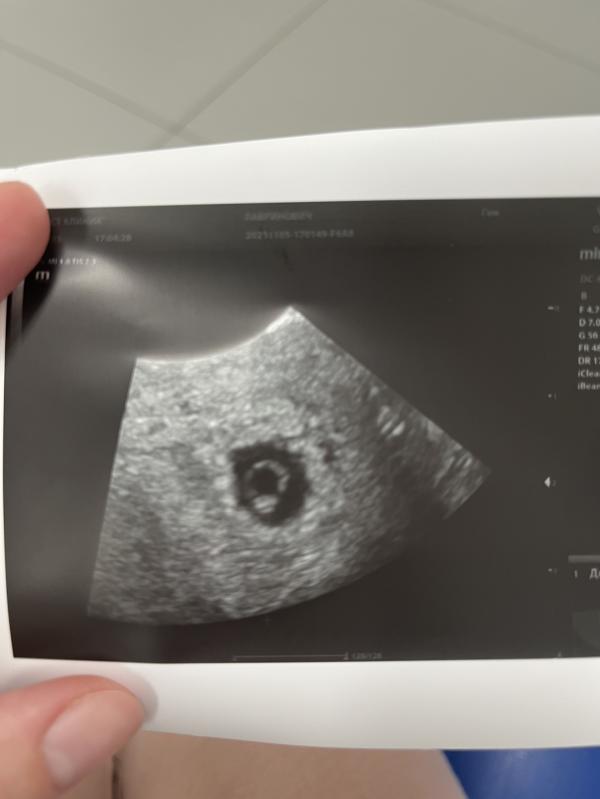

поздравляю, очень люблю эти УЗИ в 6-7 недель🤗, самое ценное бриллиантовое колечко...после трёх вообще уже всё не страшно 😉, лёгкой беременности

У меня тоже такое фото узи с дочкой )

Колечко с бриллиантиком ❤️

Бусинка ваша, как колечко с бриллиантом, мимими😍